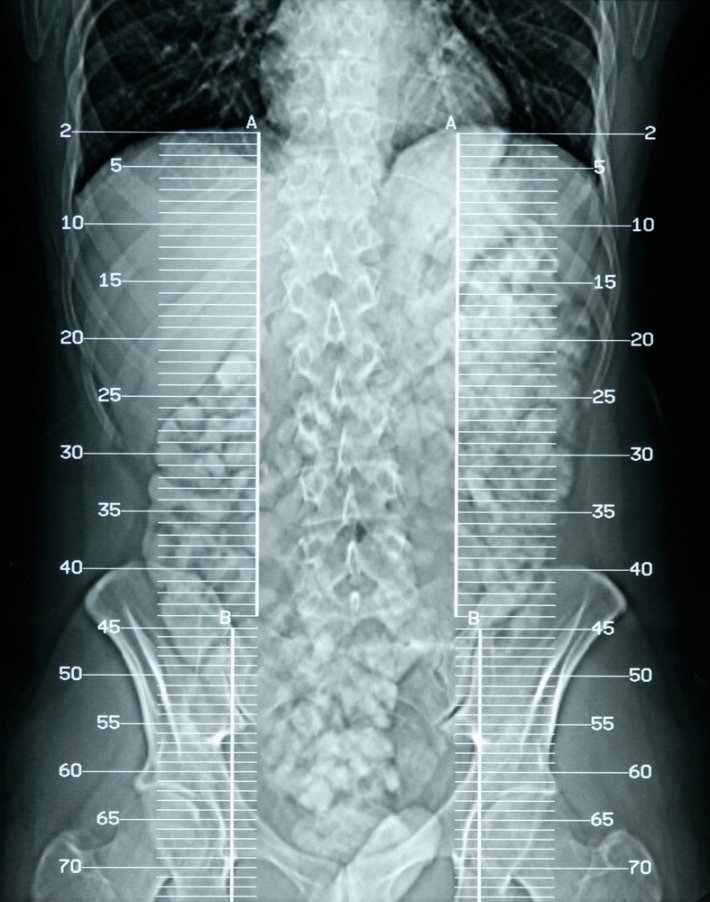

Kemik Erimesi Osteoporoz Nedir, Kemik Erimesi Tedavisi Nasıl Yapılır

Kemiklerdeki bazı dokuların azalması sebebiyle kemiğin dayanıklılığını kaybetmesi sonucunda oluşan hastalığa osteoporoz yani halk diliyle kemik erimesi denir.

Kemik erimesinin belirtileri çoğunlukla tüm hastalarda aynıdır. Bu belirtiler; omurga bölgesindeki kırılmalar, hastanın boyunun kısalması, sırt ve bel ağrıları, kalça ve bilek kemiklerinde oluşabilen kırıklar, sırtta kamburlaşma ve omuz bölgesinde yuvarlaklaşma şeklinde görülür.

Kemik erimesinde erken teşhis çok önemlidir. Eğer hastalık, erken teşhis edilemez veya teşhis koymada geç kalınırsa, ölüme ve sakatlığa neden olabilir.